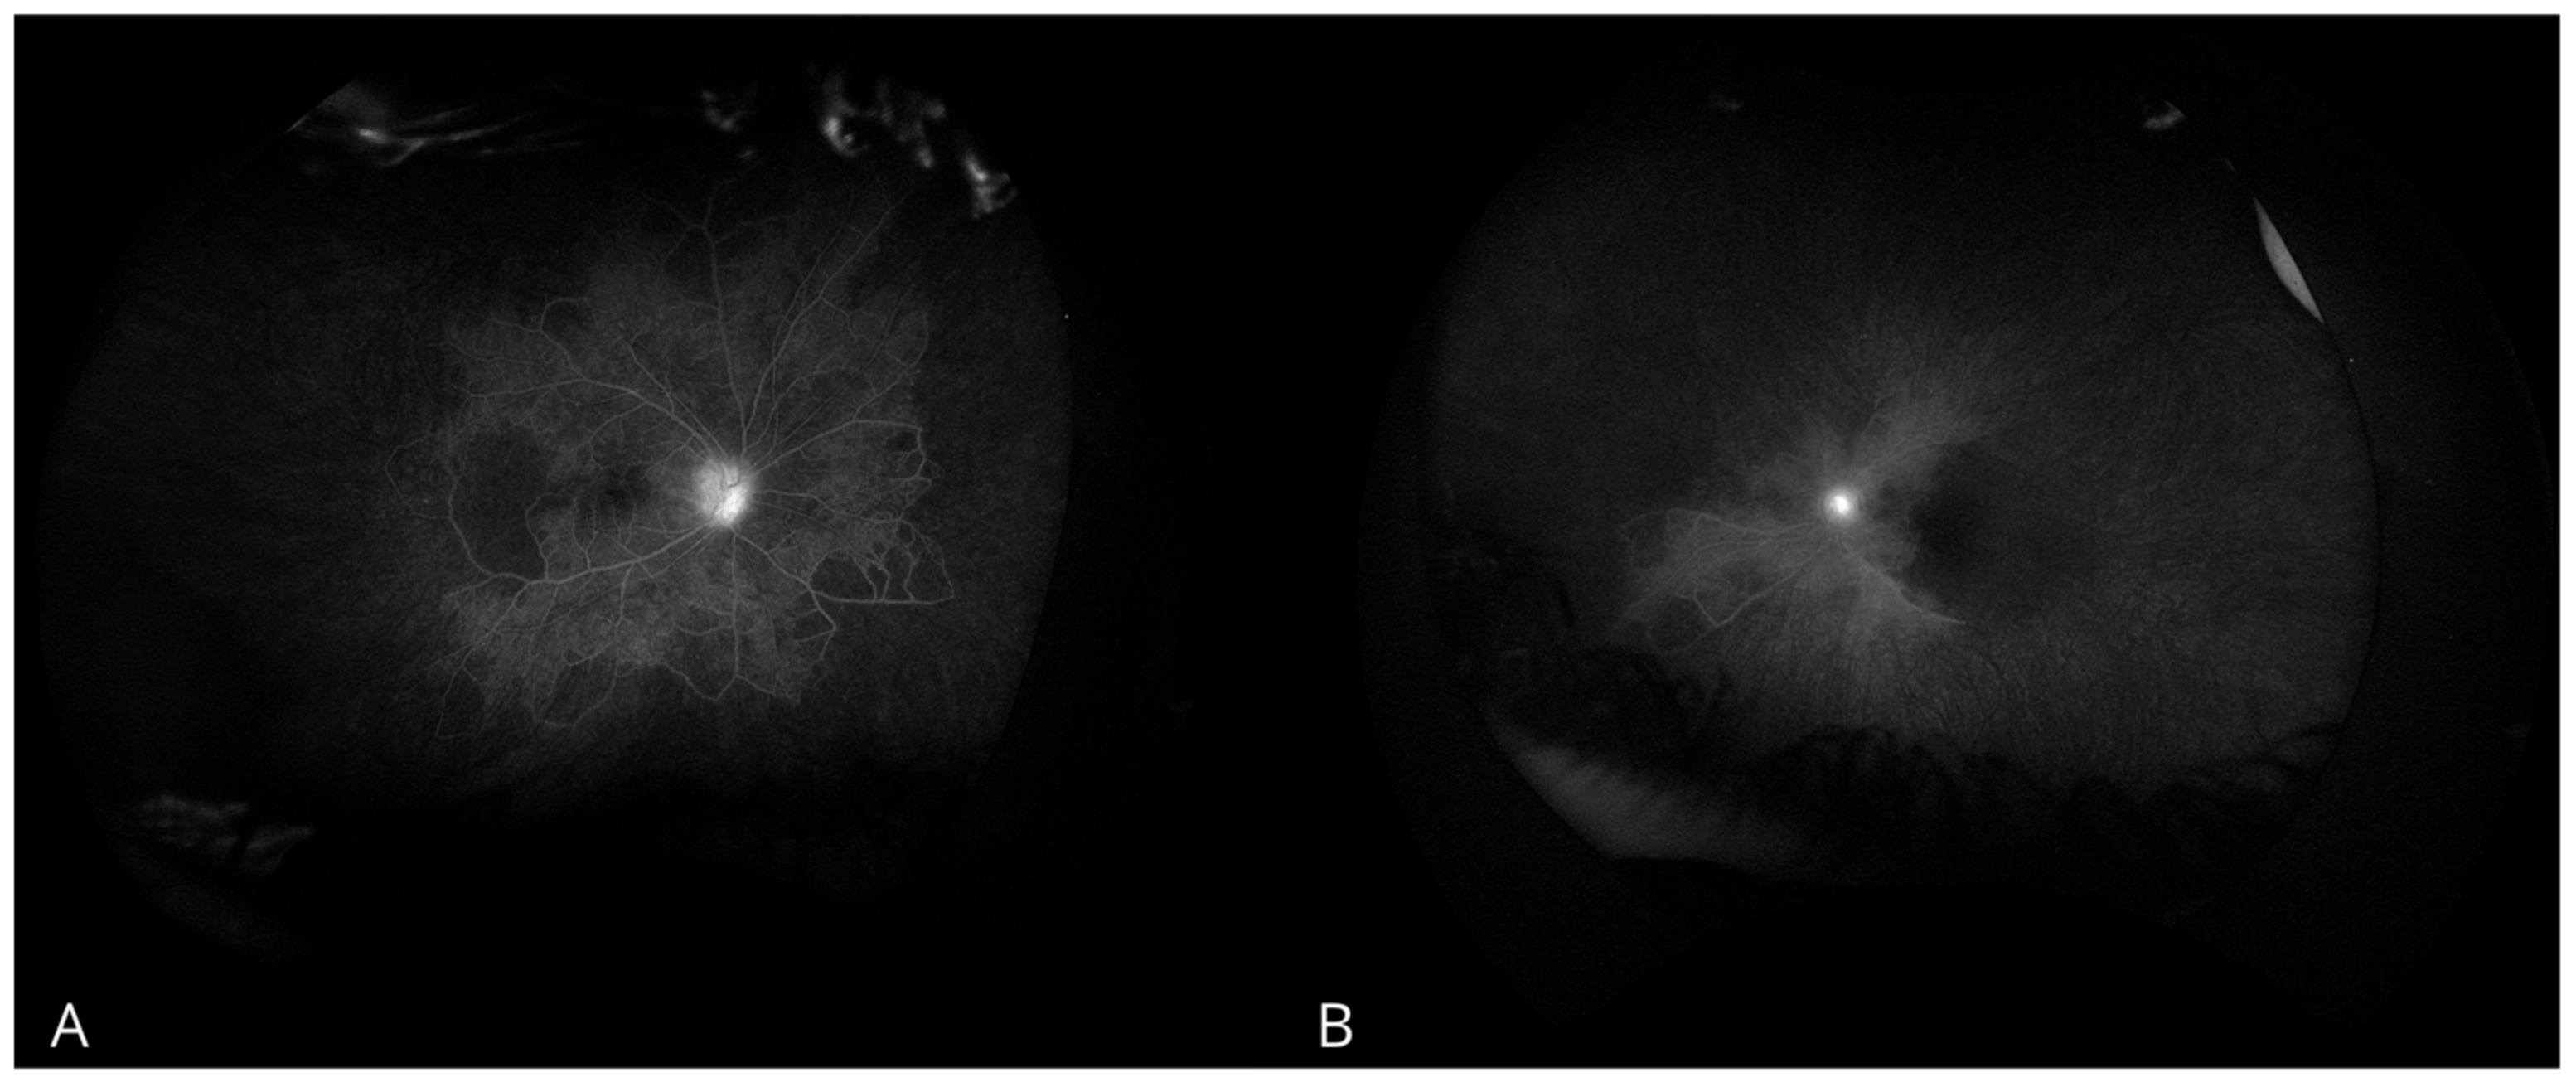

Gonioscopic examination revealed a 360° closed angle with neovascularization in the angle of the LE, while the RE had an open angle with visible neovascularization at the trabecular meshwork. Fluorescein angiography demonstrated peripheral capillary non-perfusion with marked peripheral vascular occlusion, more severe in the LE than in the RE (Figure 1). These findings, combined with elevated IOP and neovascularization were consistent with NVG.

Figure 1. Fluorescein angiography examination. (A) Right eye. (B) Left eye.